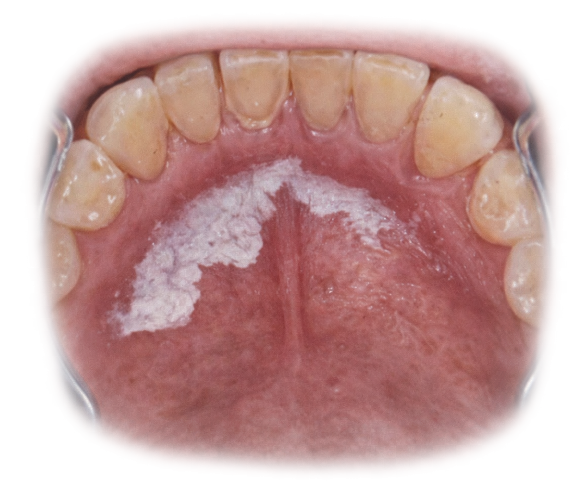

Fattori Moderni che Alterano l’Equilibrio Naturale

La rivoluzione industriale alimentare ha modificato profondamente questo equilibrio fisiologico.

- Zuccheri Raffinati e Carico Fermentabile Elevato

L’introduzione massiva di saccarosio e carboidrati raffinati( snack, bevande zuccherate) ha determinato:

- Aumento della frequenza degli attacchi acidi

- Maggiore produzione di polisaccaridi extracellulari adesivi( glucani, appiccicosi) fanno da colla ai batteri.

- Biofilm più strutturato e resistente: la saliva penetra meno, gli acidi restano più a lungo e i batteri sono più protetti.

La frequenza di assunzione è spesso più dannosa della quantità assoluta. Ogni volta che si mangiano zuccheri il pH scende. Sotto 5,5 si ha un effetto demineralizzante.

Il saccarosio è cariogeno perché è sia substratoper la produzione di acidi sia precursore di polisaccaridi extracellulari che aumentano adesione e stabilità del biofilm.